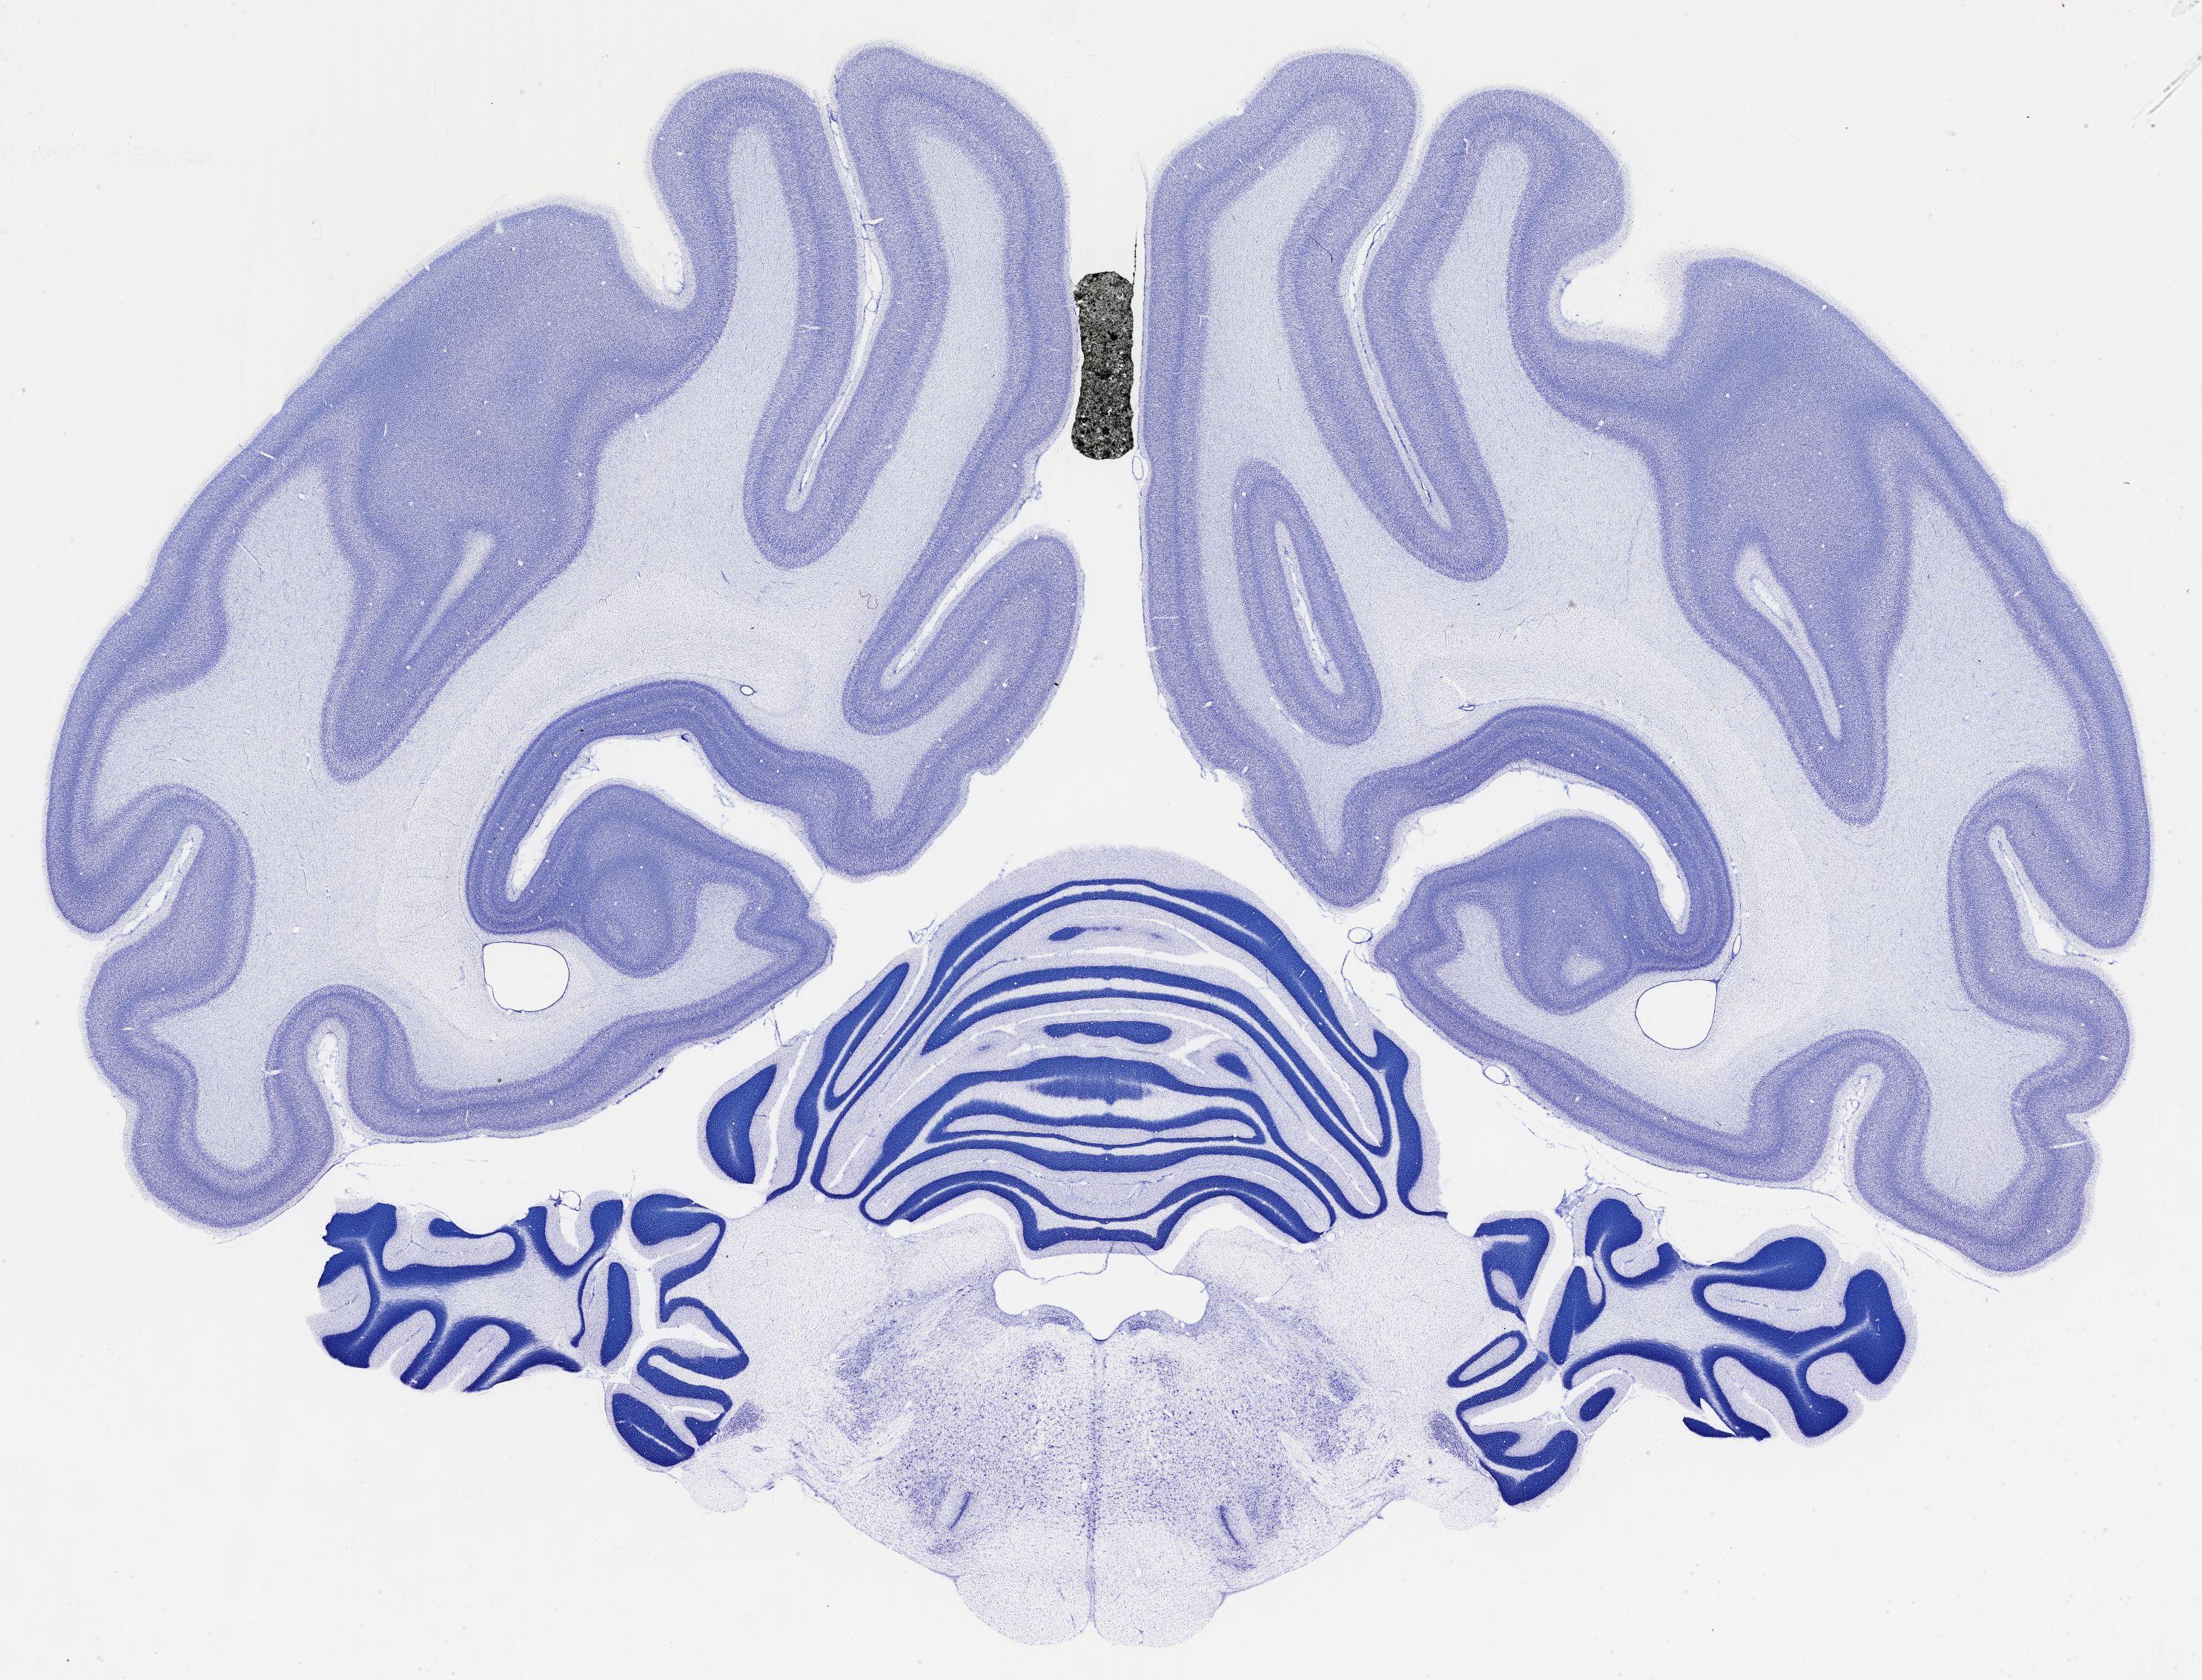

Datasets -> Chlorocebus Aethiops -> Nissl, coronal, histo, Whole-Brain, adult

[ Metadata ]   ·   Source: NeuroScience Associates

thumbnail

522